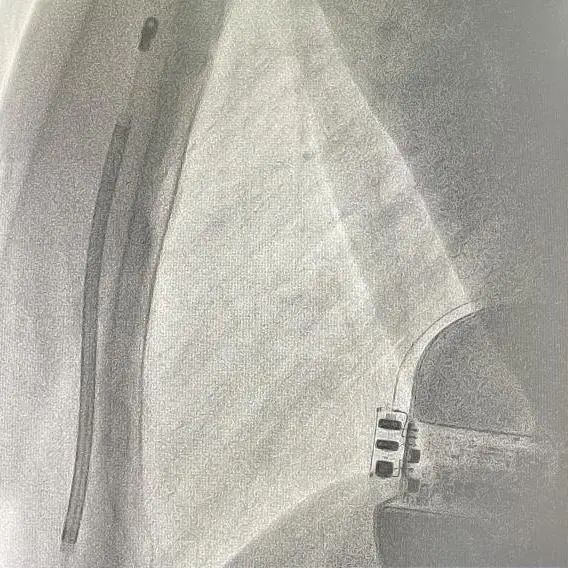

手术在全麻醉下进行。常规消毒、铺巾,取左腋中线平等第5-6肋为预定点,切开一约7cm切口,逐层将皮下组织分离直至肌层,在前锯肌与背阔肌之间寻找到深筋膜层,以确保囊袋在患者的脂肪层下并且足够容纳装置。

再次于胸骨柄右缘1cm为预定点,切开一长约4cm切口,逐层分离至深筋膜层,预埋两根缝合线用导引针,于切口间建立隧道,利用隧道针将电极沿皮下置入囊袋。再以切口位置建立隧道,同样以隧道针将导线头端沿深筋膜层,送至胸骨柄上缘(距切口14cm处,于切口处固定电极导线,囊袋处连接脉冲发生器(S-ICD A209),固定脉冲发生器于深筋膜层。

排除空气后关闭深筋膜层,进行DFT测试。两位患者均采用50HZ,200MA交流电方式进行诱颤,SICD均正确识别且65J除颤一次成功,除颤阻抗分别为85欧姆和59欧姆。缝合皮肤,术区纱布覆盖,包扎,弹力绷带加压包扎止血。手术圆满成功。第一台手术耗时2小时,第二台手术仅耗时1个半小时。

患者一:

患者二:

根据Praetorian评分,在术后影响下评估。两位患者评分均为30分。

(Praetorian评分越低,术后除颤风险越低,30分为最低分数)